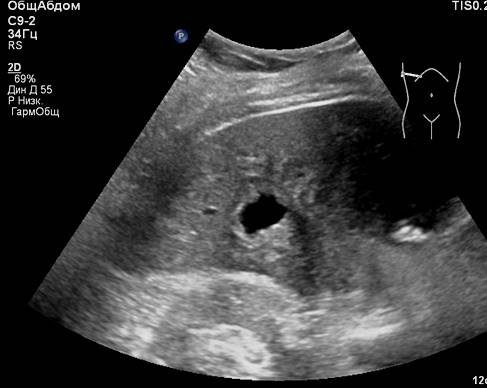

Представлены клинические наблюдения редкого осложнения эхинококкоза печени – прорыва эхинококковой кисты в желчные протоки. Осложнение стало причиной обструкции желчных протоков, механической желтухи и холангита. Освещены этапы диагностики, роль УЗИ в выявлении осложнений эхинококкоза печени, рассмотрены способы минимально инвазивного лечения с применением эндоскопических и чрескожных технологий под контролем лучевых методов.